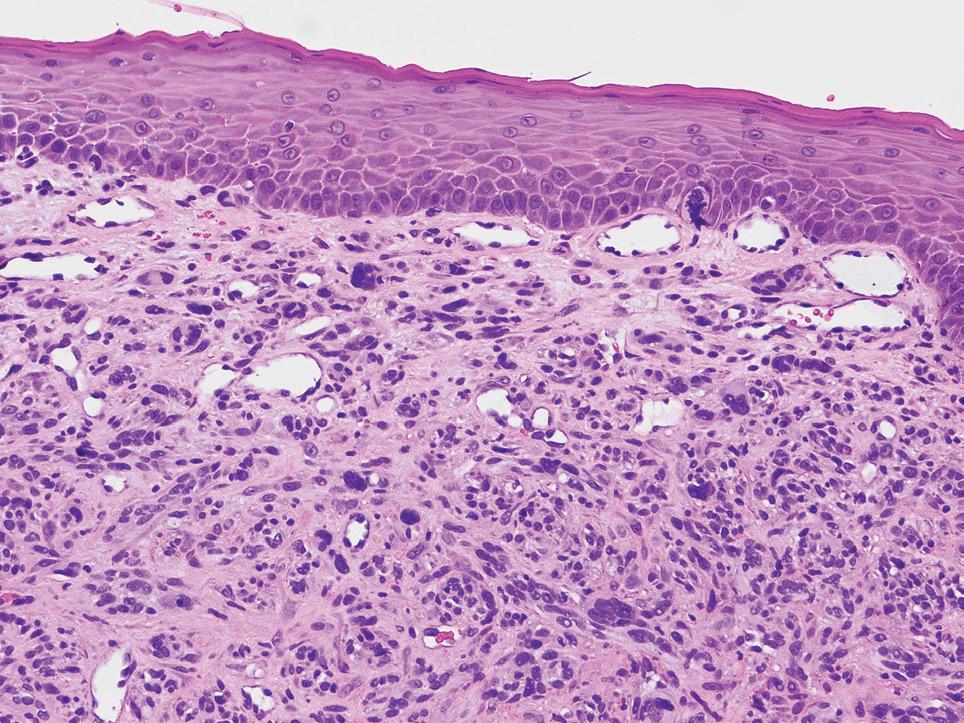

Clinical ChallengesAnswer in Oral Medicine

The correct diagnosis was:

Oral melanoma; rare oral malignancy

1 2

The lesion in question was histologically proven to be an aggressive oral melanoma. Although oral melanoma is rare, pigmented lesions in the oral cavity must be viewed with a high index of suspicion. In this case, the lesion did not contain any pigmentation and was amelanotic. Amelanotic melanomas of this size are exceedingly rare. Histologically, the lesion itself was highly dedifferentiated and multiple stains were relied upon to ascertain the diagnosis. In this instance the lesion could have very well been one of the afore-mentioned differentials and biopsy (with appropriate staining) is key to the diagnosis.

The patient’s imaging showed a large heterogeneously enhancing partly necrotic mass centred on the left maxillary tuberosity and adjacent posterior maxillary alveolar ridge, with superior protrusion into the posteroinferior aspect of the left

3 4

5

maxillary antrum, extensive aggressive erosion of the maxillary tuberosity and anterior extension within the left maxillary gingivobuccal sulcus and along the left lateral margin of the hard palate. No suspicious lesions were noted elsewhere he was sent for urgent management to his designated tertiary hospital. He was seen in a multi-disciplinary team with the plan of surgery and immunotherapy (Keytruda) as the first line option.

The dentist has played a pivotal role in giving this patient the best chance of survival. By picking up the lesion, realising the urgency and calling on the patient’s behalf to ensure his case was bought to my attention. This meant that the patient was seen, diagnosed and staged promptly.

6

1. Low power amelanotic melanoma 2. High power amelanotic melanoma 3. CT showing the extend of the lesion. 4. CT showing the extend of the lesion. 5. SOX10 showing strong diffuse staining 6. HMB45 showing patchy positive staining

Histopathological imaging: Courtesy of Dr Jason Lau, Anatomical Pathologist, Clinipath Pathology